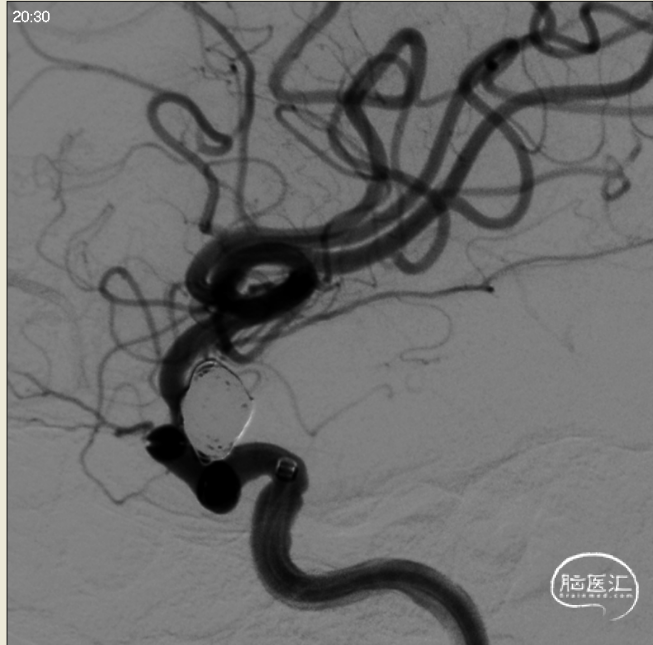

行正侧位造影及3D造影,全身肝素化后路图下将使用经塑形SL10微导管和prowler在0.14微导丝带领下超选进入动脉瘤和载瘤动脉,释放部分4.5*28支架,选用弹簧圈7枚栓塞动脉瘤,充分释放支架,造影复查显示动脉瘤被致密栓塞,载瘤动脉通畅。

栓塞结束工作位正位

栓塞结束工作位侧位

手术顺利,病人情况稳定,血压109/67mmHg,脉搏58次/分,呼吸12次/分。